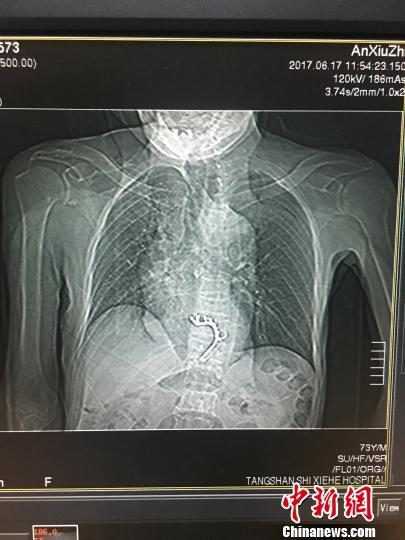

唐山市协和医院胸外科成功为唐山一县区的王老汉进行了一台复杂的开胸经食道取异物及消化道重建大手术。图为手术前王老汉胸透片。医院供图

可是,这一次老人和家人苦苦等待将近十天的时间,假牙还是一动不动地停留在食道下段一个部位。此时,老人因为自身疾病以及数日不能正常进食等原因,已经出现了胸痛,精神萎靡、心动过速等症状。家人急忙把老人送到了唐山市协和医院,经过耳鼻喉科、消化内科专家的联合会诊后,采取经胃镜试取异物手术。镜下发现,假牙托的金属卡环牢牢卡在了食道下段一动不动,而周围的食道软组织由于假牙托的压迫出现了水肿、溃疡情况。如果假牙不能及时取出,锋利的金属卡环很有可能刺穿已经溃烂的食道,一旦刺入旁边的大动脉里即可造成大出血,后果不堪设想。